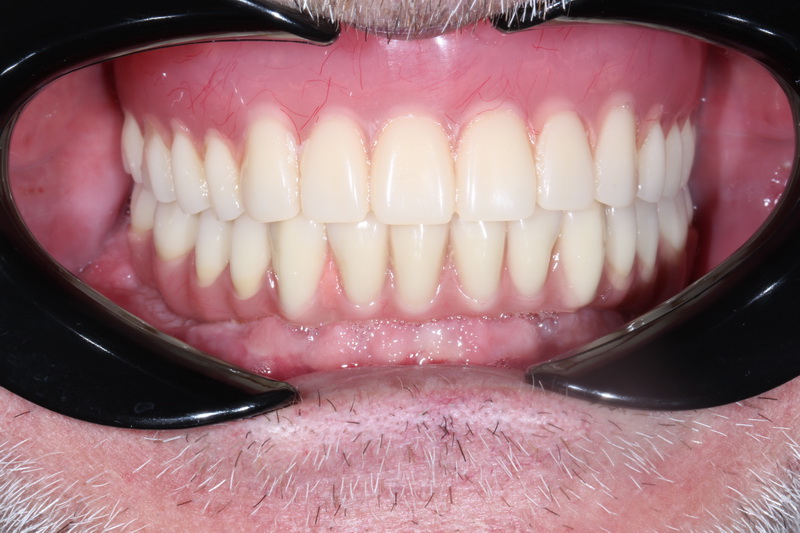

На прикладі нашого кейсу хочемо показати весь етап лікування. Що  важливо знати про All-on-4, це те, що імплантація за протоколом All-on-4 відбувається у два етапи.

В день операції було проведено лікування, це – встановлення 4-х імплантів на нижній щелепі у попередньо сплановані позиції, з подальшим негайним навантаженням тимчасовим незнімним протезом.

Пацієнт залишився задоволеним, не отримавши жодних больових відчуттів.

Пацієнт чекає  2-го етапу, через 4—6 місяців, де плануємо замінити тимчасовий протез на постійний.  Таким чином, пацієнт жодного дня не залишиться без зубів.